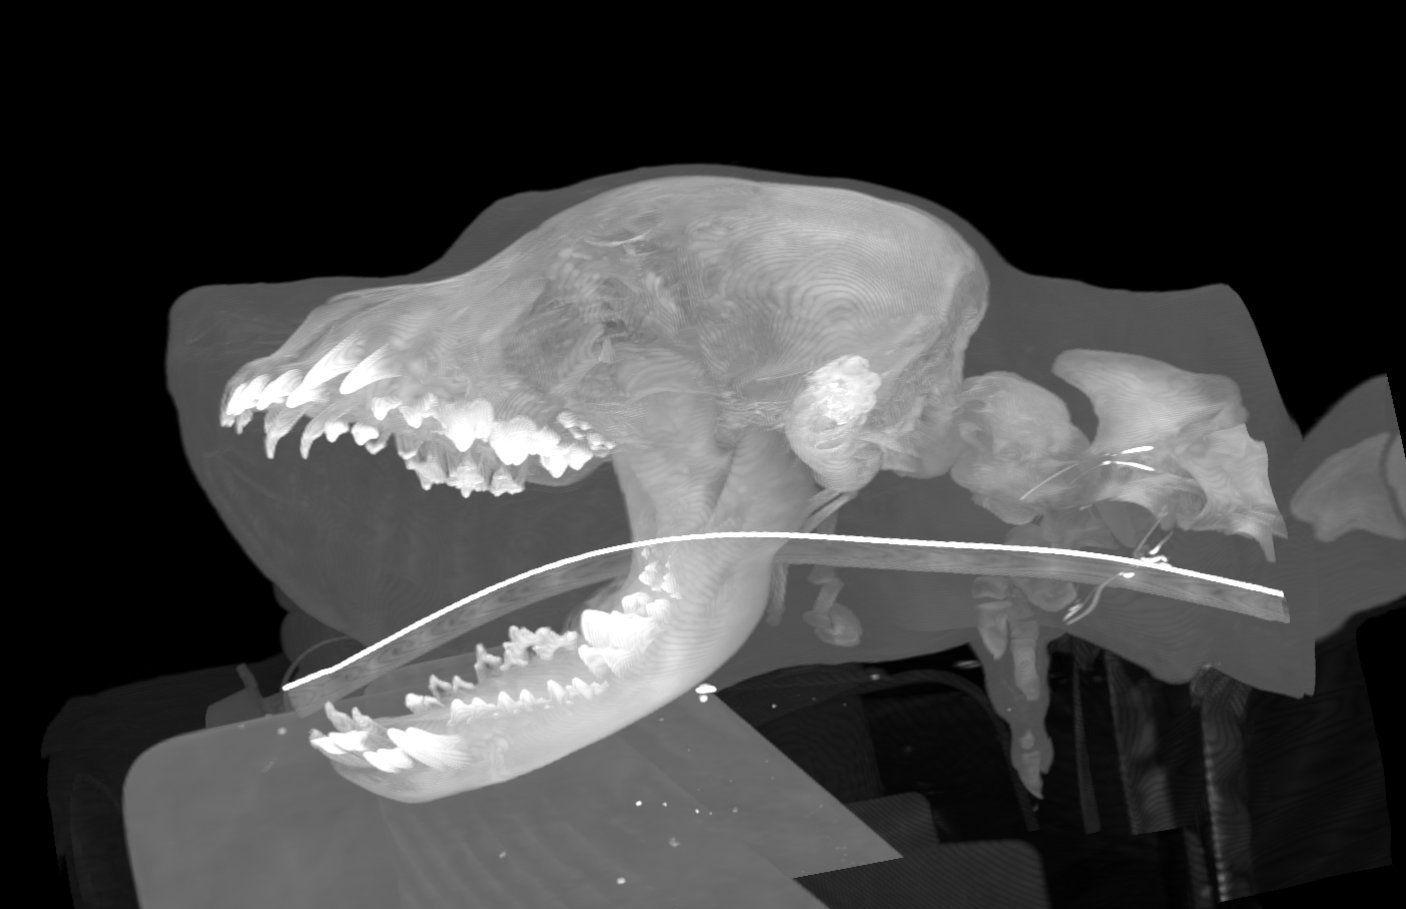

Durch den Einsatz unseres digitalen Röntgengeräts erhalten wir hochauflösende Röntgenbilder in nur wenigen Sekunden.

Diese Bilder können sofort auf einem Computerbildschirm angezeigt, vergrößert und analysiert werden. Dadurch sparen wir nicht nur Zeit, sondern können auch schnellere und genauere Diagnosen erstellen.

Darüber hinaus ermöglicht das digitale Röntgen eine bessere Bildqualität und Kontraststärke, was eine detailliertere Untersuchung der betroffenen Bereiche ermöglicht. Dies ermöglicht es uns, Krankheiten, Verletzungen oder andere Gesundheitszustände schneller und genauer zu identifizieren.